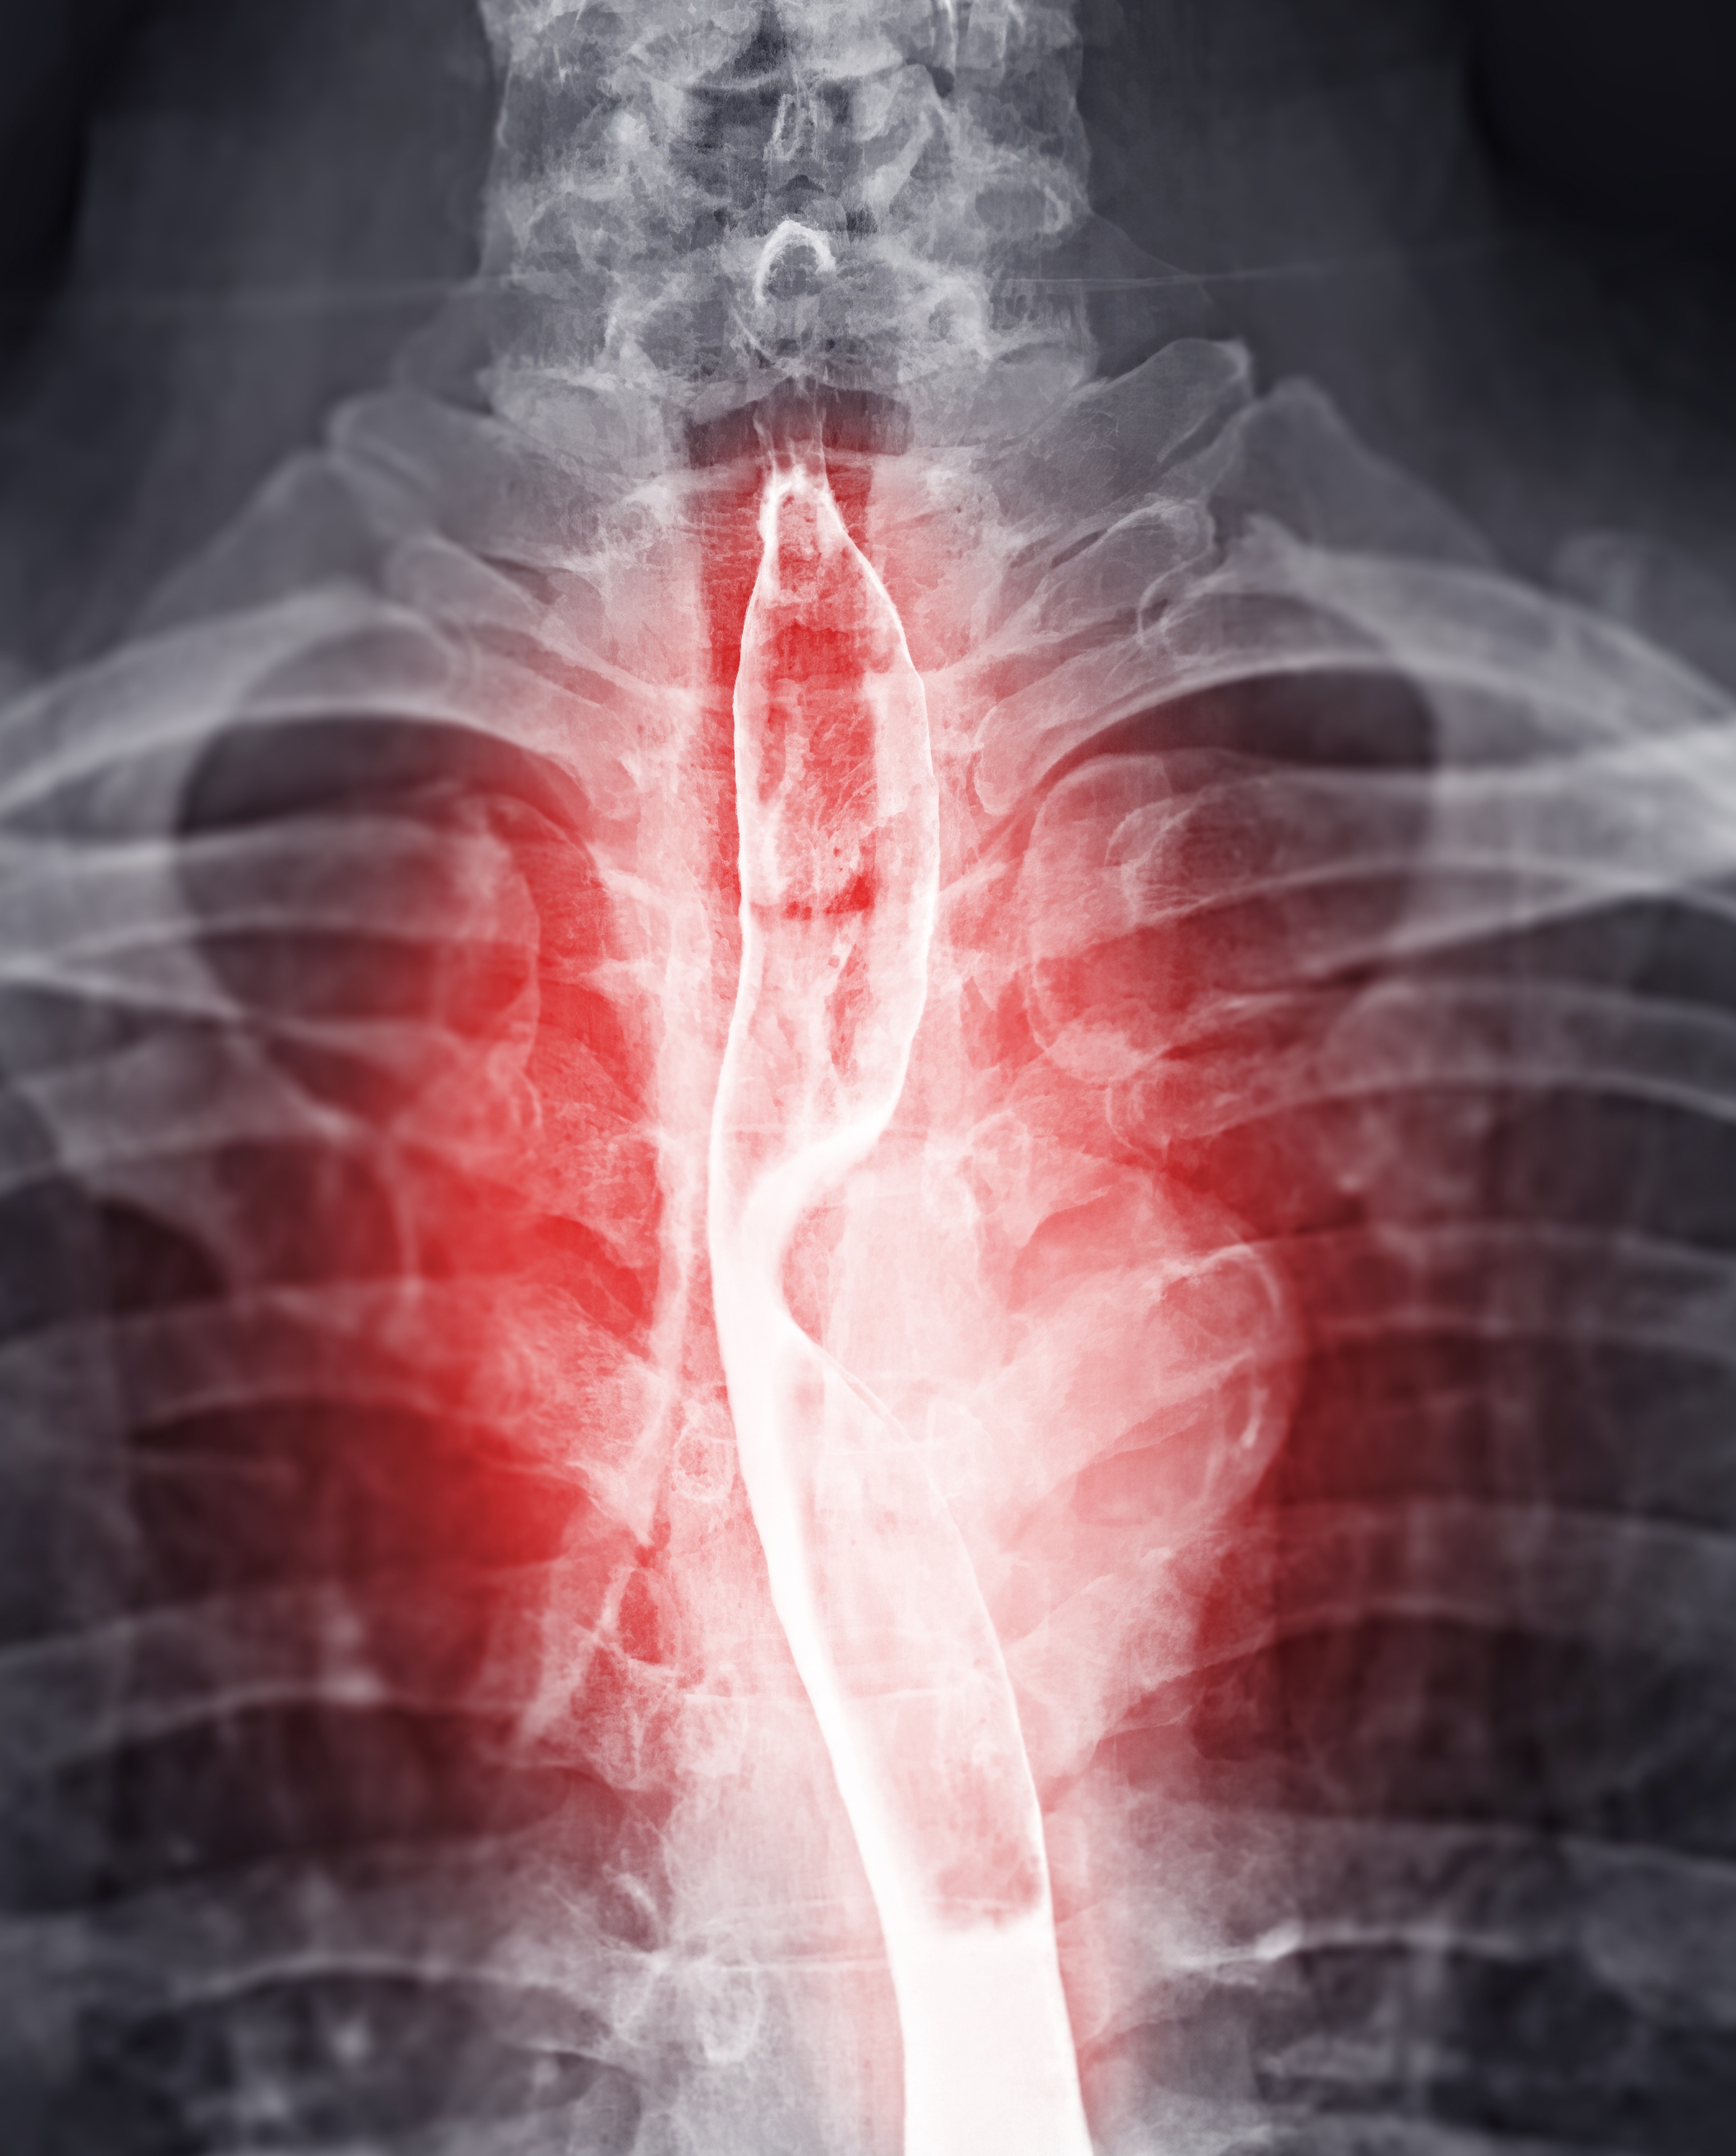

«En gang hadde en fyr kommet inn i ICU som blødde voldsomt fra munnen. Viste seg, han var som en livslang alkoholiker i alvorlig leversvikt fra skrumplever. Men blodkoagulasjonen/koagulering kommer fra leveren din. Så når hans tannlege fjernet alle tennene hans for å installere implantater, ble fyren så dårlig at han endte i ICU. Til tross for å installere implantater, ble leveren til at han ble fet i Og han døde.

«Barnelege her. En 3-åring ble innlagt i ICU. Mamma brakte ham inn fordi han var» pustet rart. «Hun var overbevist om at han hadde en medfødt diafragmatisk brokk, der membranen din ikke utvikler

«Denne gutten var 3, så alle trodde moren var gal og hadde gått ned et internett kaninhull. Men Ed fikk røntgen av brystet, og sikker nok, ungen hadde mageorganer i brystet på venstre side, fikk diagnosen medfølelse av membranen som den eldre brokk, og gikk til den eller for å reparere. Mamma visste at det var diagnosen, fordi den eldre broren overlevde det samme og det samme og det samme, og det var å gjøre det som den eldre. uten symptomer.

«Jeg innrømmet en middelaldrende kvinne til ICU for hjertetamponade. Hun fikk en presserende perikardiosentese med perikardial avløpsplassering. Ingen visste hvorfor hun utviklet perikardial effusjon, men vi fikk en CT som viste flere lungeknuter, så antakelsen var at hun hadde kreft.»